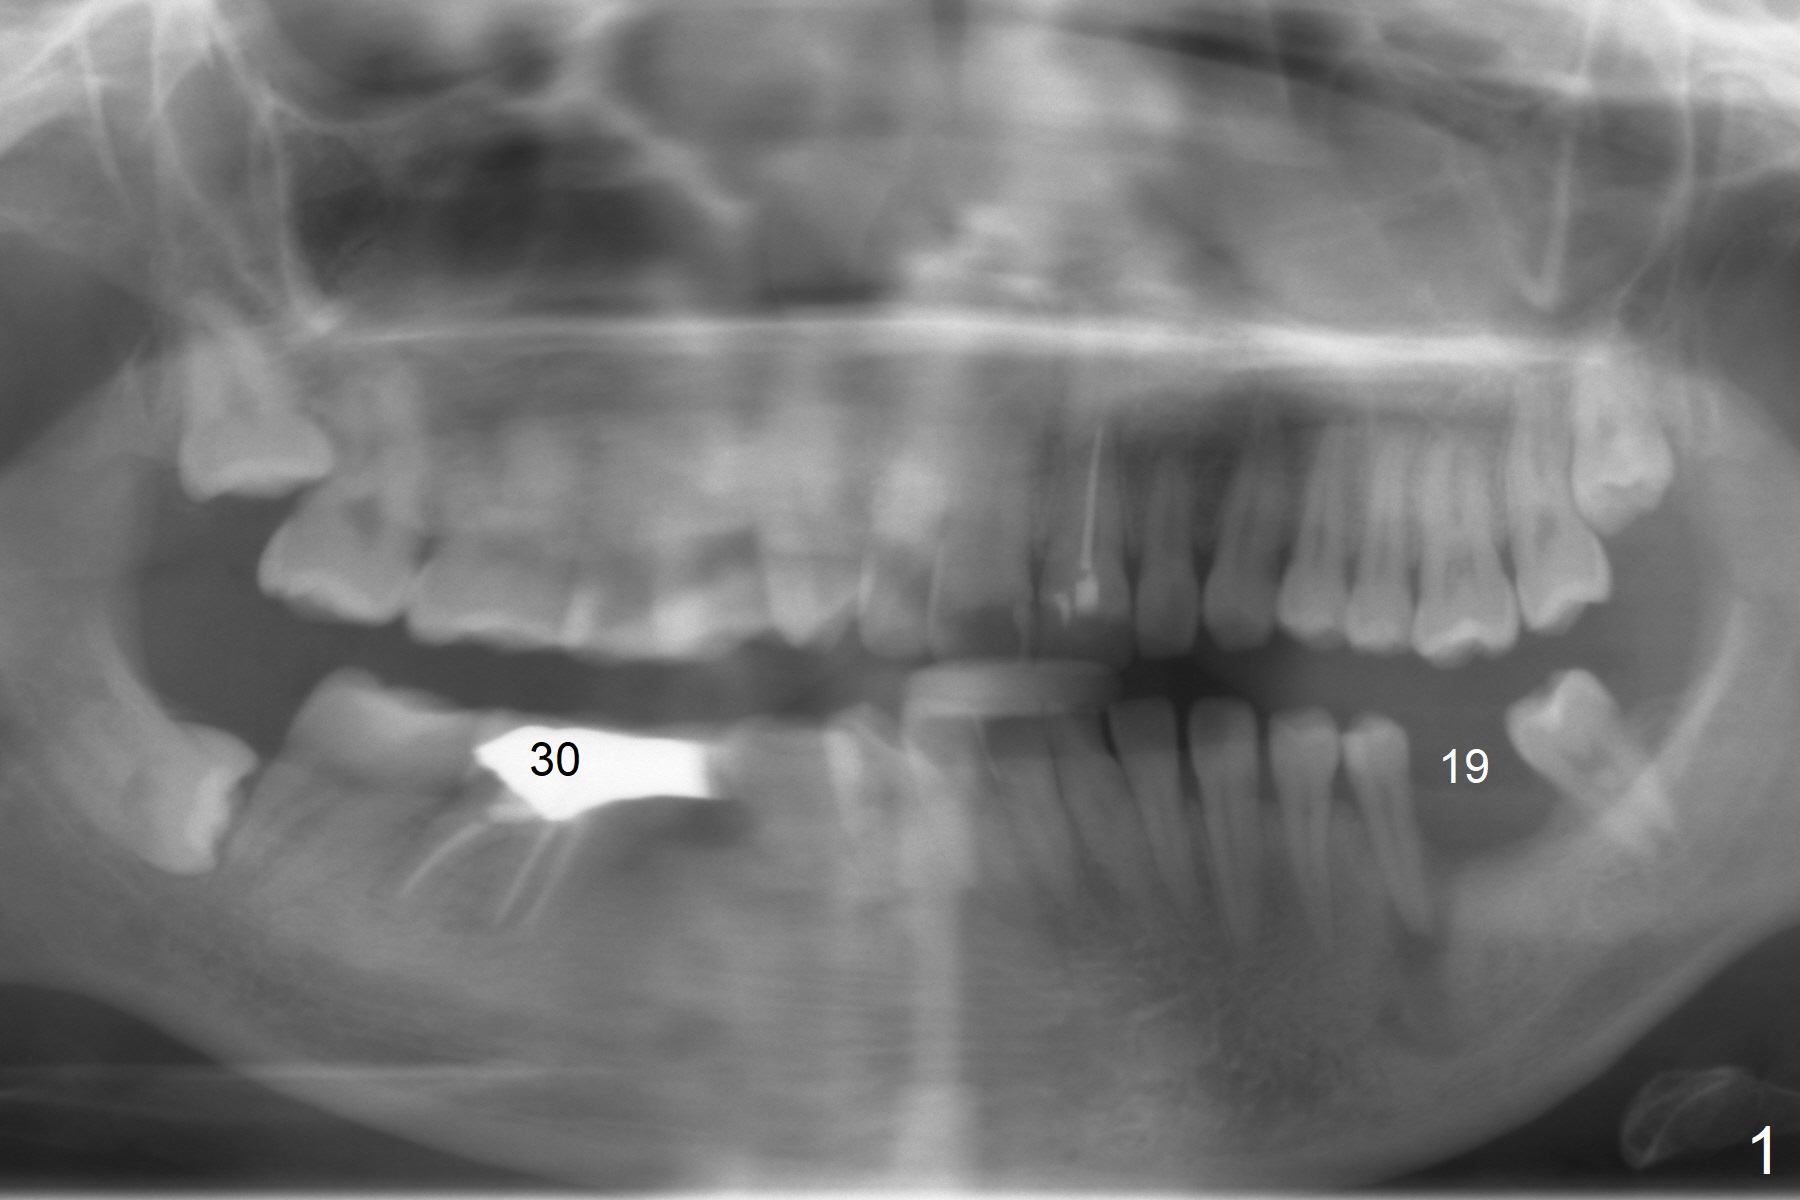

A 41-year-old slender woman returns for #29 and 30 implants (Fig.1,2) because of a fistula mesiolingual of #30 (Fig.3 arrowhead) several years post RCT. There is no deep pocket at #30. In fact the distolingual canal is missing (Fig.2 (black arrow),3 (DL)). RCT retreatment should solve apical periodontitis. Due to long term of missing #19 and 29, the mesiodistal space is limited with diastema between #28 and 29 (Fig.1, 2 (white arrowhead)). Limited ortho appears necessary prior to, during or post implantation. The ridge at #19 and 29 is not only narrow, but also short. It seems appropriate to place short 2- and 1-piece implants, respectively (Fig.5,4). As a matter of fact, there is open margin of the crown at #30 (data not shown). If the crown is to be removed prior to RCT, implantation is conducted before ortho, since the provisional can be made narrow mesiodistally.